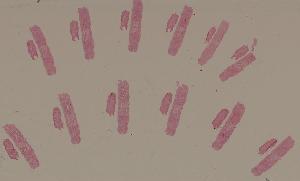

高倍视野